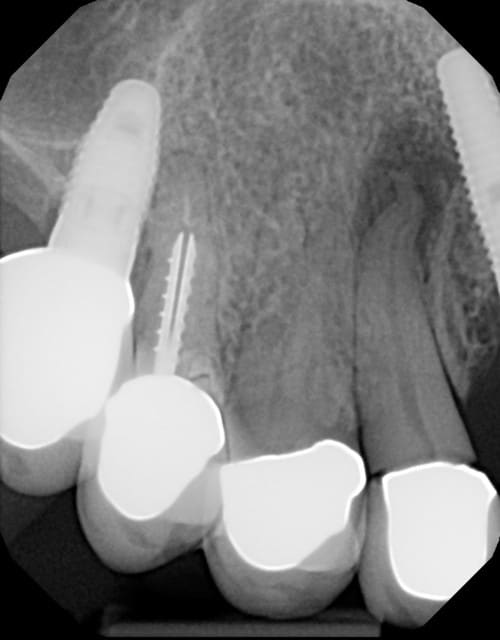

Patiente adressée pour évaluation :

son dentiste ne sait que faire.

À l'examen :

13 : belle fistule vestibulaire, mobilité, carie cervicale

14 : mobilité +++

15 : fracture racine (?), carie cervicale

Les implants datent de 5-6 ans (par un autre CD, la patiente a depuis déménagée).

Le bas , pas touche cette année, on verra en 2012.

Votre plan de tx ?